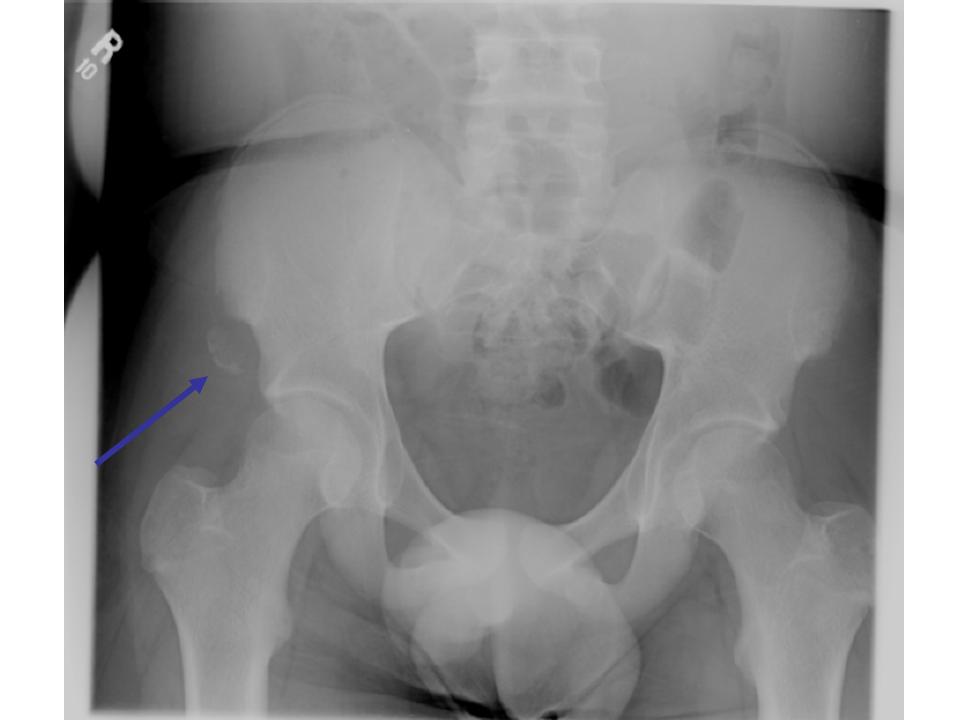

Avulsion Fracture of the Anterior Superior Iliac Spine

ED Management

Non operative treatment is generally recommended for avulsion injuries to the ASIS and AIIS. Advise rest, ice, and NSAIDS. When in bed, a position that avoids tension on the affected muscle should be advised. The patient can bear weight as tolerated with crutches for additional comfort. Refer for a routine orthopaedics follow-up. Athletic activities can resume when the patient is able to participate without pain.